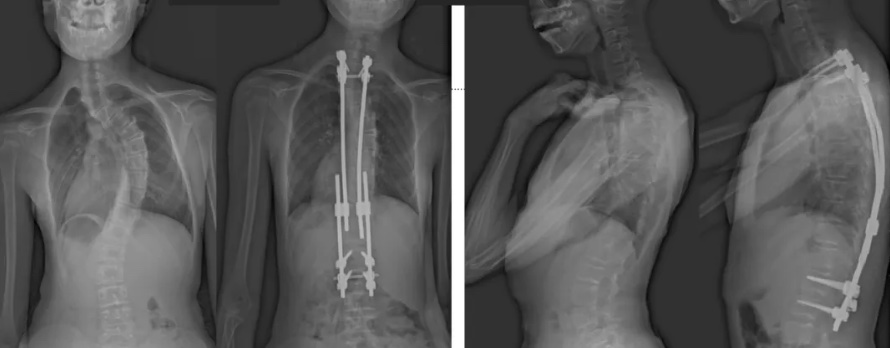

白瑪?shù)恼恍g(shù)前、術(shù)后對(duì)比圖(左側(cè));側(cè)位術(shù)前、術(shù)后對(duì)比圖(右側(cè))

術(shù)后第二天,白瑪就下地活動(dòng)了。媽媽驚喜地發(fā)現(xiàn),白瑪一下子“長高”了近十厘米,重新抬起了頭,挺直了脊梁,肩膀也不歪了,可謂“脫胎換骨”。媽媽激動(dòng)地錄制了一段白瑪走路的身影,把喜悅分享給全家。白瑪?shù)男g(shù)后檢查也提示,手術(shù)成功,恢復(fù)良好。

白瑪今年10歲,正在讀小學(xué)。媽媽發(fā)現(xiàn),白瑪經(jīng)常歪著肩膀,在反復(fù)提醒“站直了,別歪著”后,情況也沒有改善。近半年來,白瑪?shù)挠覀?cè)肩胛骨逐漸向后凸出。到醫(yī)院檢查后發(fā)現(xiàn),白瑪?shù)男刈荡嬖诿黠@的側(cè)凸畸形,是早發(fā)型特發(fā)性脊柱側(cè)凸。由于側(cè)凸較為嚴(yán)重,已經(jīng)失去了支具治療的機(jī)會(huì)。小白瑪才10歲,隨著身體的不斷成長,她的脊柱會(huì)越來越彎,肩膀會(huì)越來傾斜。這不僅影響體態(tài)和外觀,也可能限制心、肺等內(nèi)臟器官的發(fā)育,導(dǎo)致心肺功能下降、肢體活動(dòng)不便,出現(xiàn)癱瘓,甚至死亡。對(duì)于白瑪這種情況,只能利用手術(shù)治療來矯正脊柱、阻止骨骼畸形進(jìn)展。

經(jīng)過術(shù)前的精心準(zhǔn)備和反復(fù)推演完善每個(gè)細(xì)節(jié),蔡思逸團(tuán)隊(duì)順利為白瑪施行了“生長棒”矯形手術(shù)。這例耗時(shí)僅1.5小時(shí)的手術(shù)也是西藏本地完成的第一例使用“生長棒”技術(shù)來治療脊柱側(cè)凸的手術(shù)。